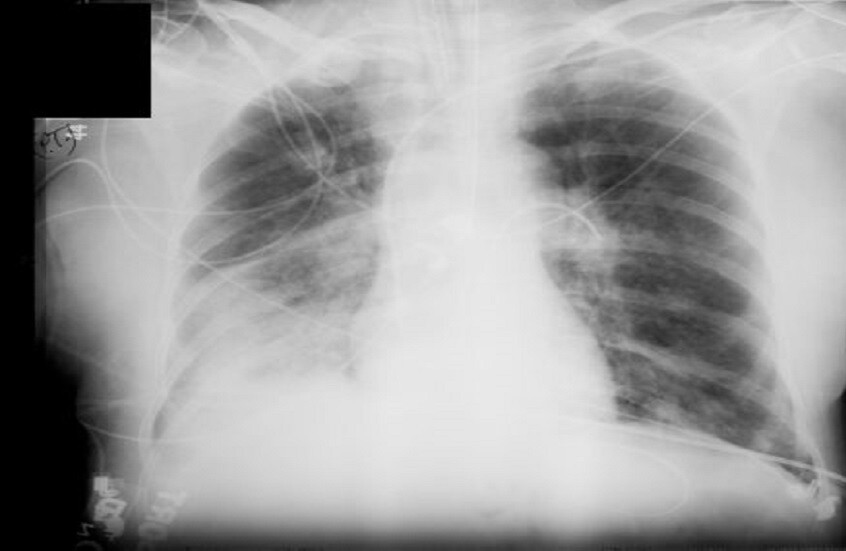

السوسنة - أفادت الدكتورة أوكسانا بلاتونوفا أخصائية الأشعة، أن الأشعة السينية لا تزال أداة تشخيصية مهمة، ولكن لا تزال المخاوف تحيط بها.

وتوضح الطبيبة، لماذا قد يكون رفض الفحص أكثر خطورة على الشخص من الإشعاع نفسه.

ووفقا لها، يستخدم الإشعاع فقط في أنواع معينة من الفحوصات، ولا تتضمن جميع طرق التشخيص التعرض للإشعاع. فمثلا، يستخدم التصوير بالموجات فوق الصوتية والتصوير بالرنين المغناطيسي وهذه طرق آمنة تماما حتى للنساء الحوامل. أما الأشعة السينية فتستخدم فقط في التصوير الشعاعي، والتصوير الفلوري، والتصوير المقطعي المحوسب، بينما لا تتضمن طرق أخرى التعرض للإشعاع.

وبالإضافة إلى ذلك، تصدر الأجهزة الحديثة جرعات ضئيلة. أي لتلقي الإشعاع الضار، يتطلب الأمر الخضوع لمئات عمليات المسح المتتالية - وهو أمر مستحيل في الممارسة العملية. وللمقارنة، تصدر أشعة الأسنان السينية حوالي 30 ميكروسيفرت، وتصدر أشعة الفلوروغرافي (fluorography) حوالي 500 ميكروسيفرت، و تعتبر الجرعة التي تزيد عن 50 ألف ميكروسيفرت سنويا خطيرة.

وتقول: "الأشعة السينية هي إشعاع كهرومغناطيسي، مثل الأشعة فوق البنفسجية والضوء والحرارة. صحيح قد تلحق جرعاتها العالية الضرر بالخلايا، كالذي تسببه حروق الشمس. وأن الاستلقاء تحت أشعة الشمس على الشاطئ دون حماية أخطر بكثير من تصوير بالأشعة السينية للصدر مرة واحدة سنويا".

وتؤكد بلاتونوفا، أن عدم اكتشاف المرض أخطر بكثير من الخضوع للأشعة السينية، حيث المعدات الحديثة تقلل من المخاطر، كما أن الفحوصات في الوقت المناسب تسمح بالكشف السريع عن الأمراض وبدء العلاج.